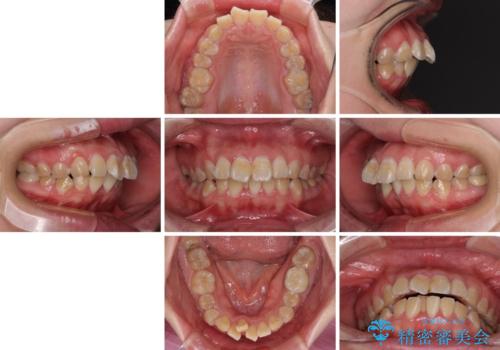

- 20代女性

- クリアブラケット

- 2年4ヶ月

- 口元の閉じにくさと、前歯のでこぼこの歯並びを気にして来院された患者様です。

口元を積極的に引っ込めるために、上下左右の小臼歯計4本を抜歯することとしました。

4本の歯を抜歯したことで、飛び出していた口元が引っ込み、横顔が大きく改善されました。